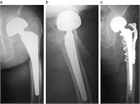

1. ⼈⼯股関節置換術(total hip arthroplasty、THA)後⾻折は種々の外⼒により発⽣するが、minor traumaによるものが多く、その発生率は一次THA後で約3.5%と報告されており、THA施行数の増加に伴い今後さらに増加すると予測される。

1. ステムの固定性が良好である場合は、ロッキングプレート、Dall-Miles cable grip system、ワイヤー、スクリューを用いた骨接合術が推奨される(推奨度1)

1. ステムに弛みを認める場合は、再置換術と骨接合術を行う(推奨度1)